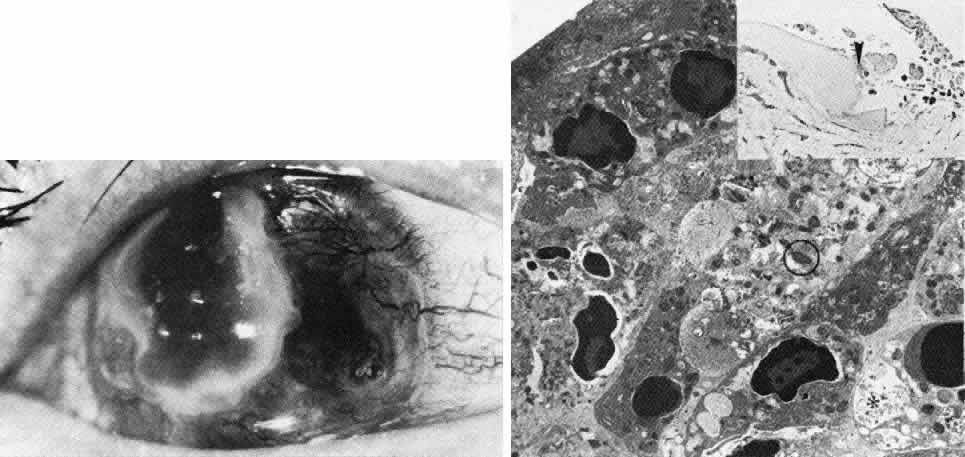

Fig. 8. Reis-Bucklers dystrophy. Top left. Slit lamp photograph of eye of 26-year-old woman with recurrent erosions exhibits typical superficial reticular opacities. Top right. Phase-contrast microscopy demonstrates degeneration of dark-staining basal cells and fragmentation of Bowman's layer (*) by nodular fibrous pannus (paraphenylenediamine, × 800). Bottom. Transmission electron micrograph confirms thin remnants of disarrayed Bowman's layer (B) and apparent continuity (at arrowhead) between basal cell cytoplasm (E) and degenerate cellular debris (D) within Bowman's layer. Basement membrane complexes are discontinuous and lack anchoring fibrils (× 30,000).

The pathogenesis of Reis-Bucklers dystrophy is unknown. The primary lesion may be due to fragmentation of the collagen fibrils of Bowman's layer, and the epithelial lesion may occur secondarily.85 Alternatively, immunofluorescent localization of laminin and bullous pemphigoid antigen suggests a primarily epithelial disease.86 Destruction of Bowman's layer and its replacement by fibrillar material are the defining changes in this disease and unequivocally distinguish it from other anterior dystrophies. Concomitant abnormalities in the epithelial basement membrane account for recurrent erosive episodes.49,87–91